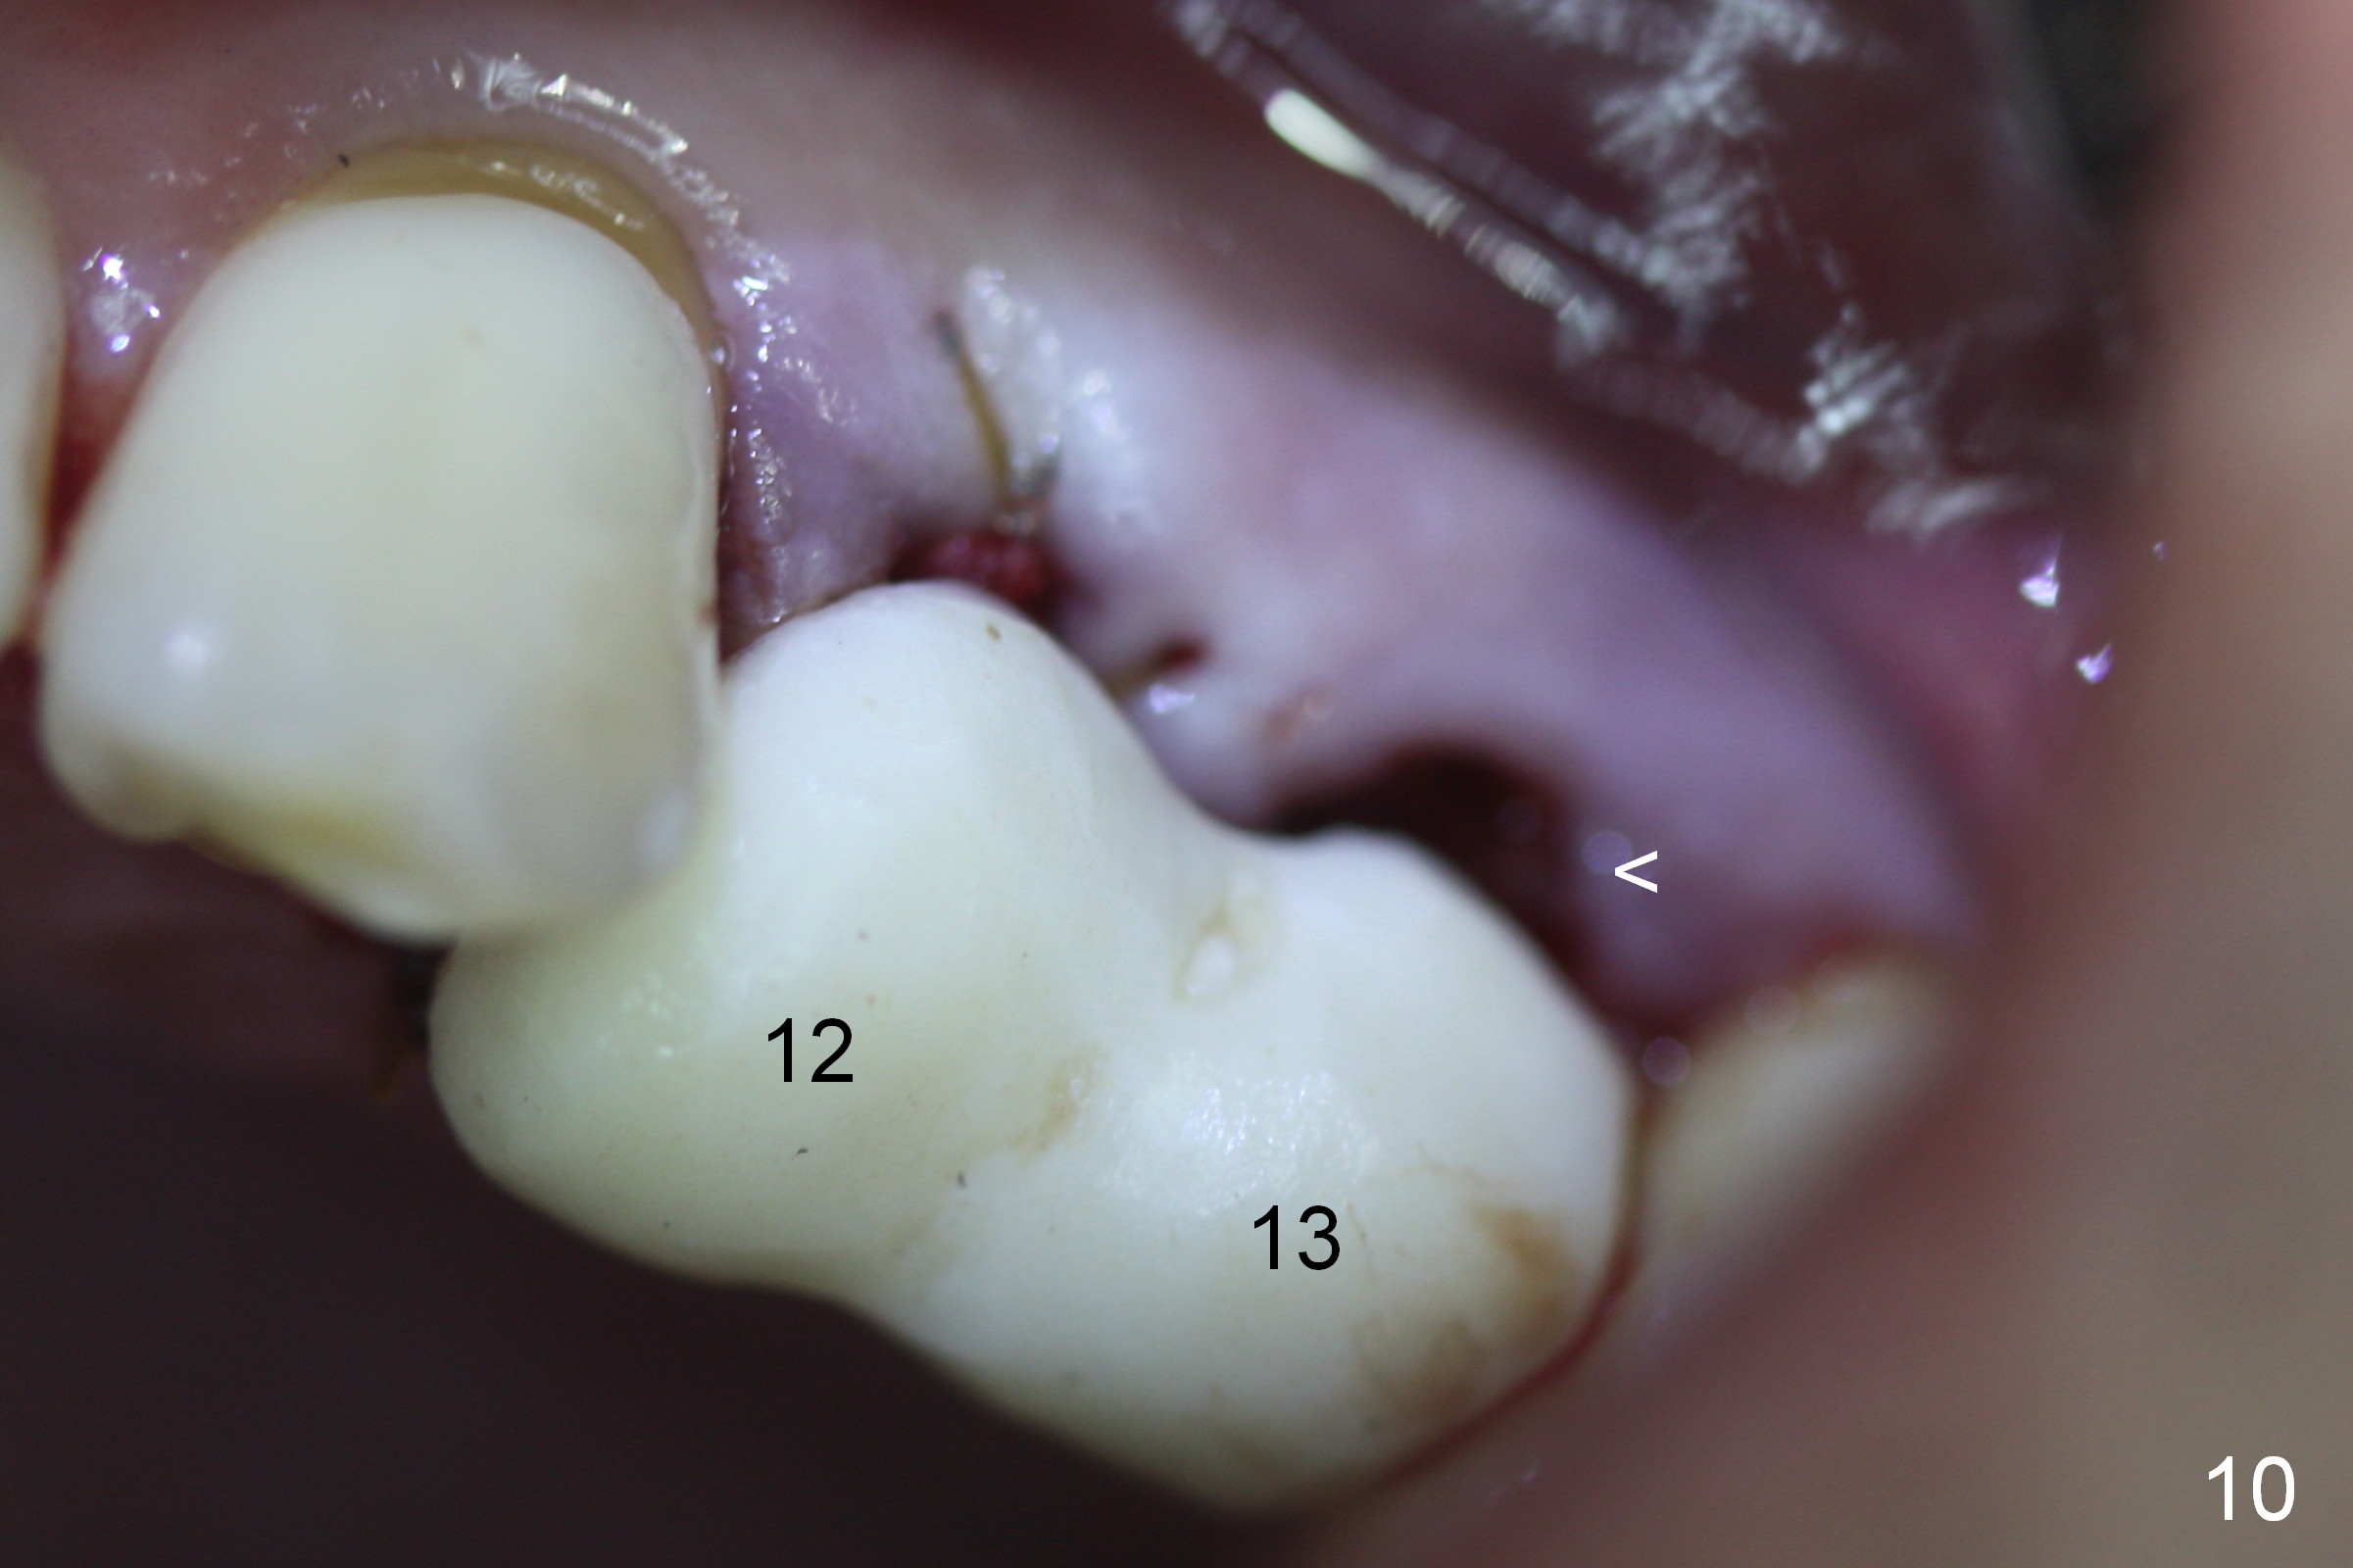

Taking 2 additional PAs with sensor 1 is frustrating (Fig.1,2), no apices shown.  Osteotomy is done smoothly with 2 mm pilot drill at 20 mm, 2.5 mm reamer at 17 mm, and 3 mm reamer at 14 mm and 4.5x20 mm tap at 17 mm.  The 1st intraop PA is taken with sensor 1 when 2 of 4.5x20 mm implants are placed (Fig.3); the implant at #12 is close to the root of the tooth #11.  The 2nd PA is taken with sensor 2: the apex of #11 touches the implant at #12 (Fig.4).  There is no separation when panoramic X-ray is taken (Fig.5).  Effort is exerted to re-direct the osteotomy twice (Fig.6: tap; Fig.7: implant) without success.  When the implant is removed, a PA is taken; it appears that the root of the tooth #11 has no damage (Fig.8).  To obtain the best recovery, socket preservation is carried out with 50/50 cortical/cancellous allograft mixed with Osteogen (Fig.12 *) and Collagen Dressing (Fig.9: #12).  A 2 (or 3)-unit provisional bridge (Fig.10: #12,13) is fabricated over the implant (Fig.9 I)/abutment (A) to cover these 2 sockets.  After acid etching #11 D surface (Fig.9 >) and relining (Fig.11 *), the provisional bridge is bonded to the tooth #11 (Fig.11,12 black >) so that bone graft will be less likely dislodged.